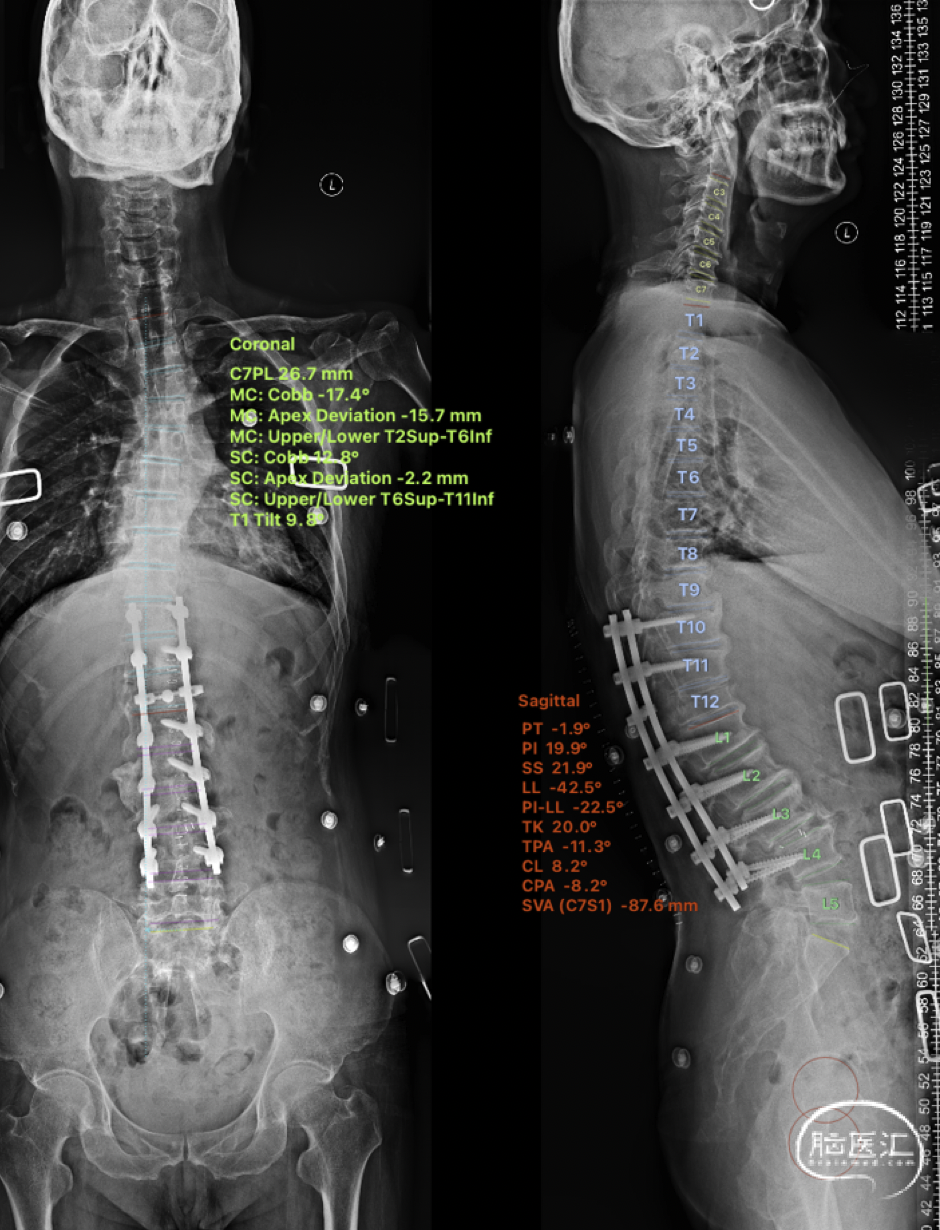

术后影像学检查

后脊柱全长片

🔺SVA -87.6mm,TK 20°,Cobb 17.4°,C7PL 26.7mm

术后CT

术后MR